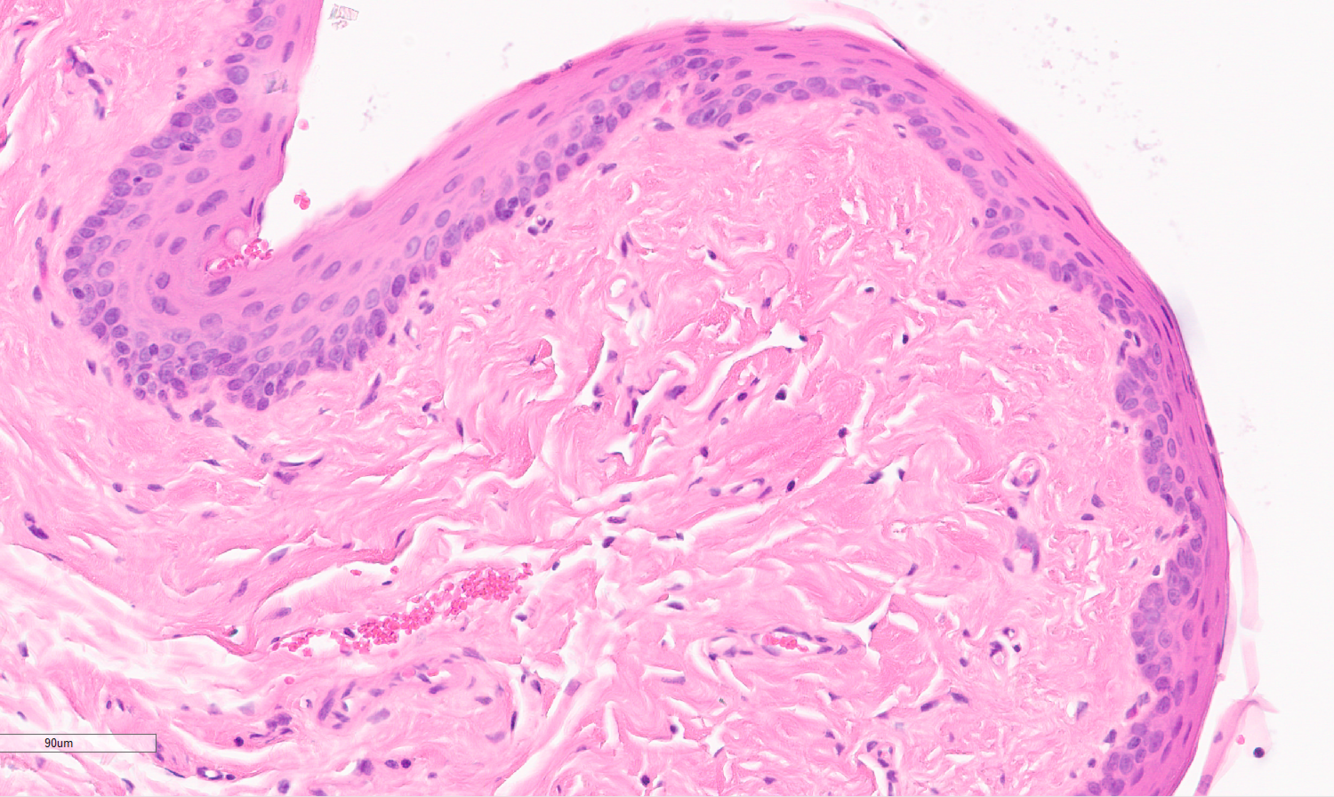

Identify this structure:

A

Viral papilloma

This is from the skin of the left elbow, provide a morphological diagnosis for this mass.

skin mass, left elbow: viral papilloma, exophytic